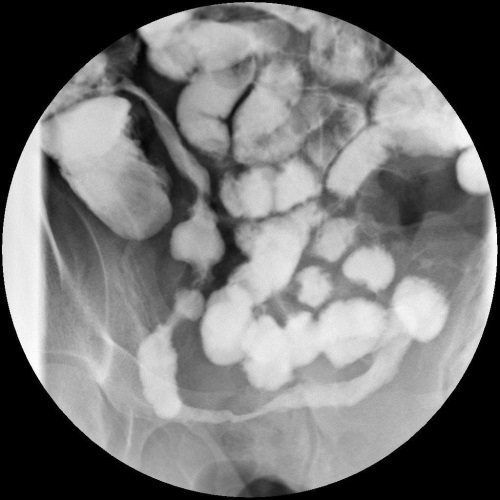

Barium study is shown from a patient with worsening Crohn’s disease. Long segment of narrowed terminal ileum in a ‘string like’ configuration in keeping with a long stricture segment. Termed ‘Kantor’s string sign’.